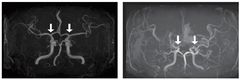

"조금만 걸어도 다리가 저려요"…반복되면 '이 질환' 의심

아침 산책을 즐기던 60대 남성 A씨는 최근 들어 걸음이 점점 짧아지는 변화를 느꼈다. 예전에는 별다른 불편 없이 동네 한 바퀴를 도는 데 무리가 없었지만 어느 순간부터 조금만 걸어도 다리가 저리고 당기는 증상이 반복되기 시작했다. 잠시 멈춰 서거나 벤치에 앉아 쉬면 통증이 가라앉았지만, 다시 걷기 시작하면 이내 같은 증상이 되풀이됐다. A씨는 처음에